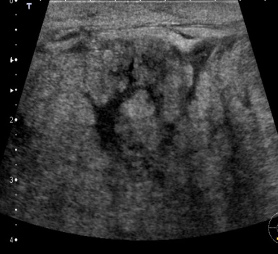

Identify this image.

Breast abscess